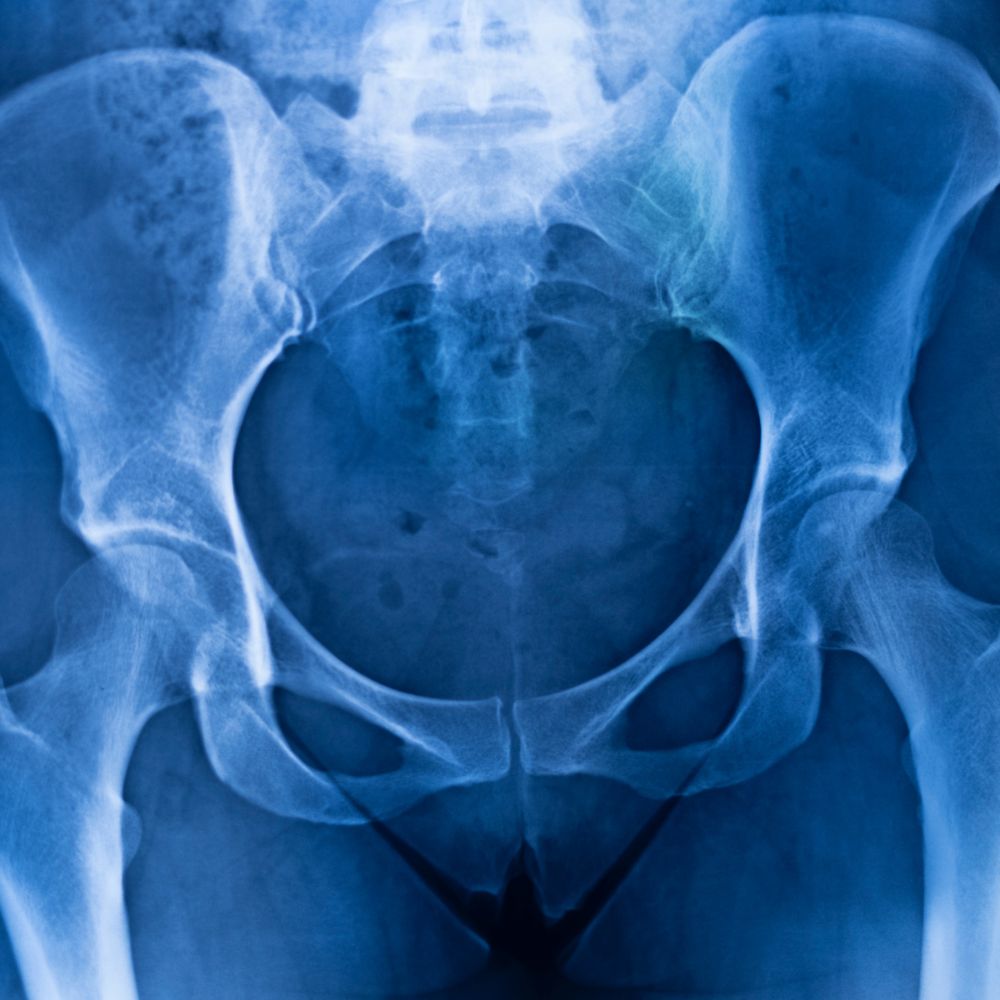

3. 골반염 진단 방법

정확히 진단하기 위해서는 여러 검사 방법이 사용됩니다. 증상만으로는 다른 질환과 구별하기 어려울 수 있기 때문에, 다양한 검사를 통한 종합적인 평가가 필요합니다.

3-2. 검사 방법

골반염 진단을 위한 주요 검사 방법은 다음과 같습니다:

- 골반 초음파: 난관난소농양 등의 합병증 여부를 확인합니다.

- CT 또는 MRI: 심한 경우나 진단이 불확실한 경우 시행할 수 있습니다.